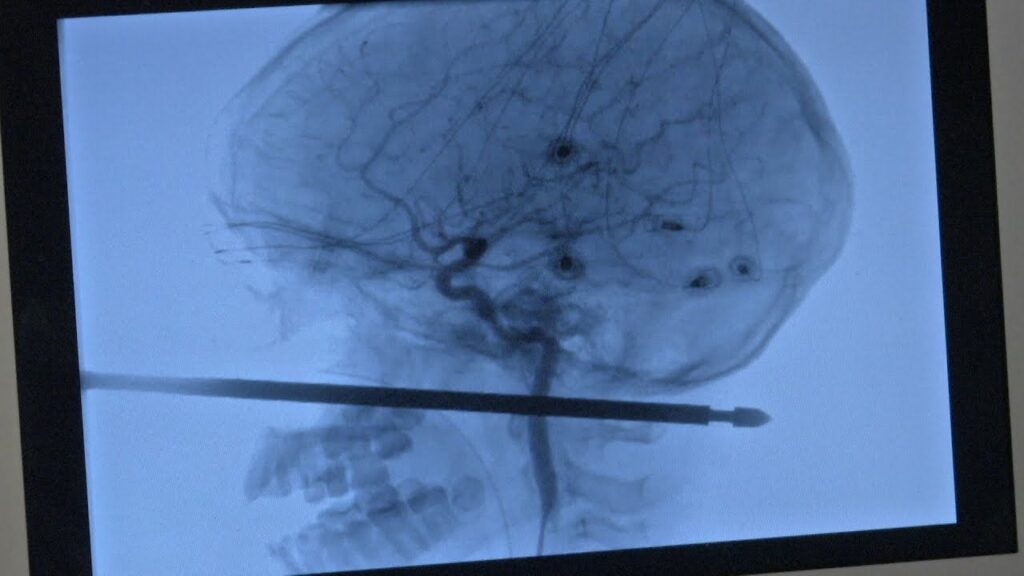

A la lista de los tipos más duros del planeta ha llegado un nuevo rey al que le auguramos años de vigencia. Su nombre: Ivan Krausouski, bielorruso de 36 años. El tipo pasará a los libros de historia como el hombre que llegó a la sala de urgencias con medio árbol atravesándole el cuerpo mientras…